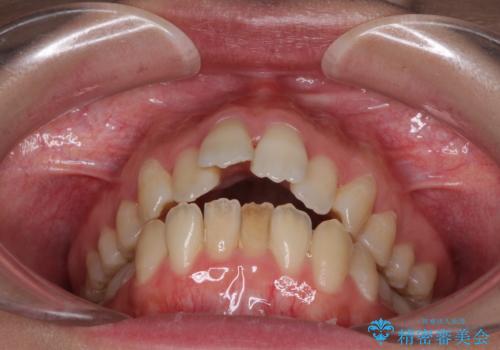

- 口元の突出感を気にして来院された患者様です。

上下左右の第一小臼歯4本を抜歯して口元を下げる治療計画としました。

舌の突出癖が強く、口元を引っ込める力に拮抗してしまい、抜歯スペースを閉じるまでに時間がかかりました。

また途中出産もありましたが、無事に治療を終えることができました。